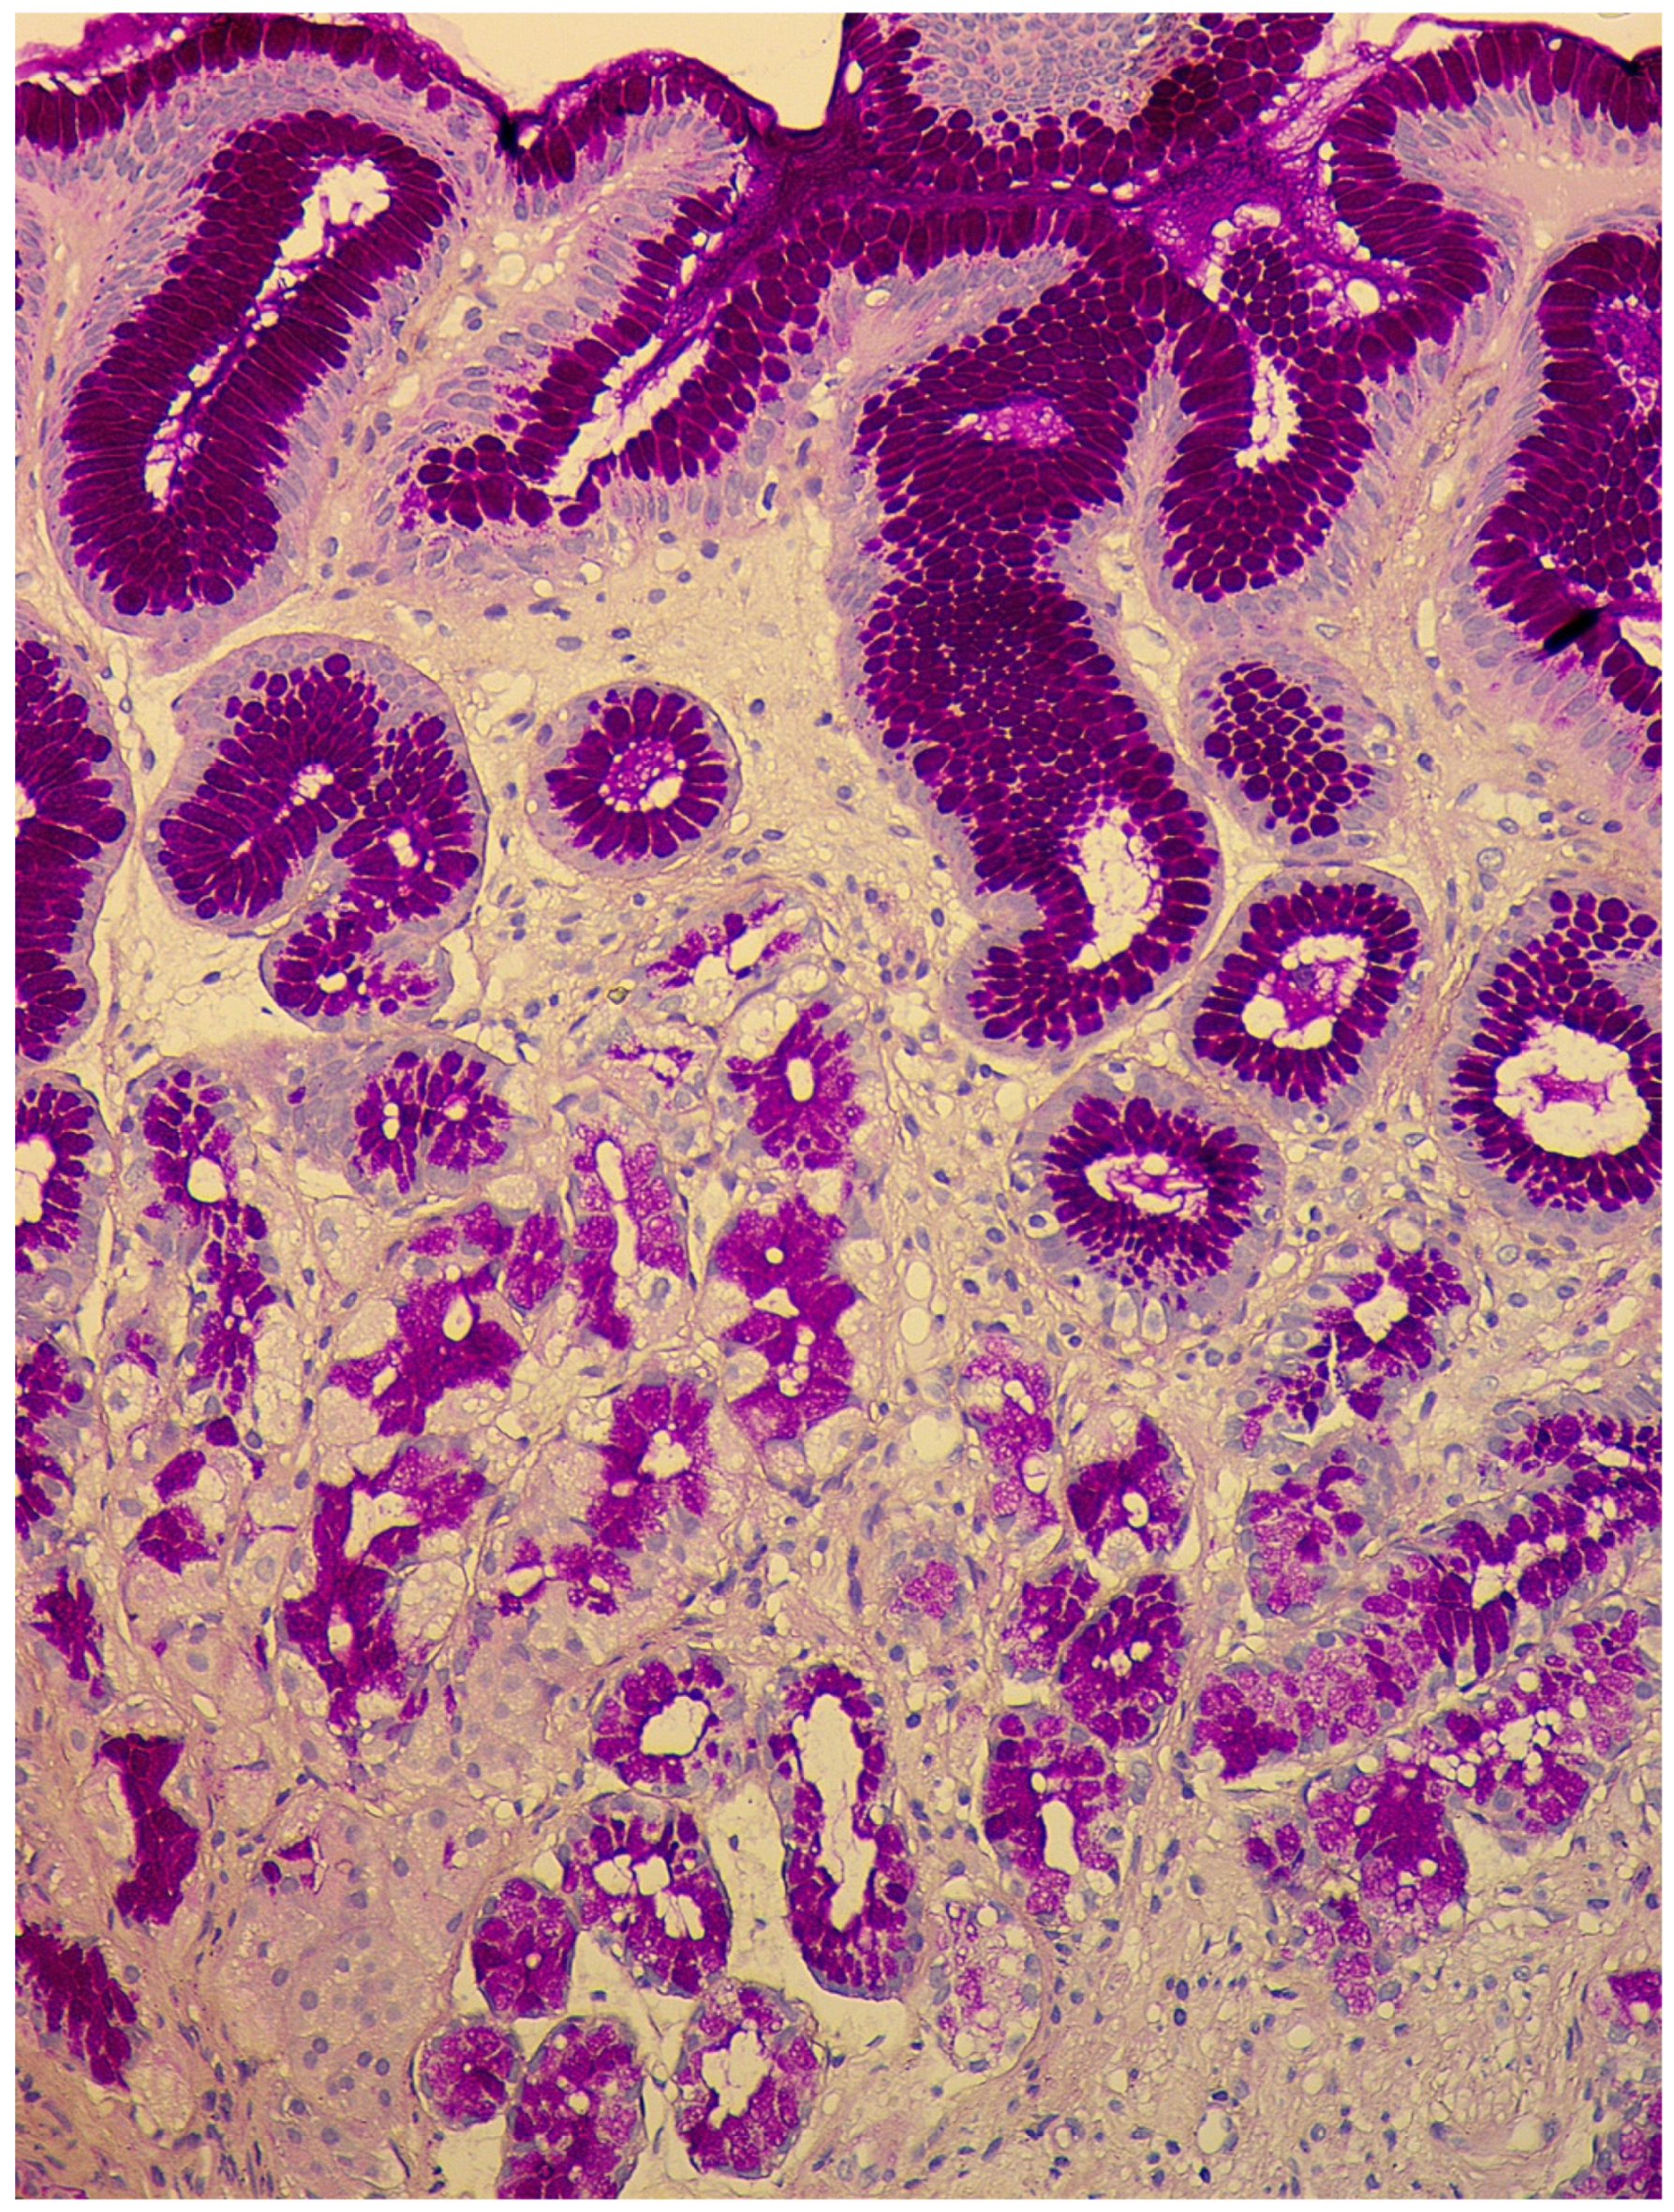

- Simple diffuse hyperplasia. This is characterized by a more than two-fold increase in the population of ECL cells. Diagnosis is difficult due to the lack of clear quantitative criteria. The diagnosis is poorly reproduced on biopsy material.

- Linear hyperplasia. The presence in one visual field of at least two groups of linearly located neuroendocrine cells, consisting of five or more cells. Usually, changes are diagnosed in the area of the neck glands (Figure 4).

- Micronodular hyperplasia. The presence of the cells’ cluster in contact with the basement membrane, but not exceeding the diameter of the gland, up to 150 μm in diameter, or a similar cluster located freely in the lamina propria of the mucous membrane.

- Adenomatous (adenomatoid) hyperplasia. The presence of an aggregate of five or more clusters (Figure 5).

- Neuroendocrine cells dysplasia. Merging clusters with diameters of more than 150 µm but less than 500 µm.